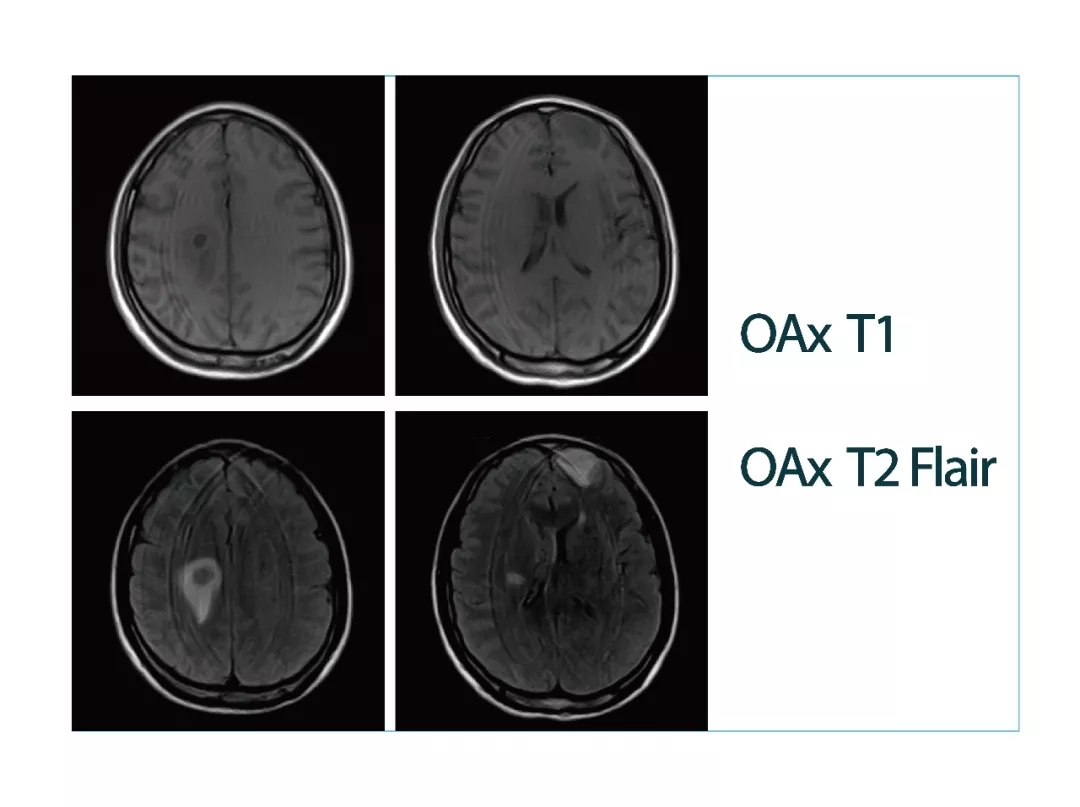

【朗润影像档案】磁共振影像病例分享(编号20180413)